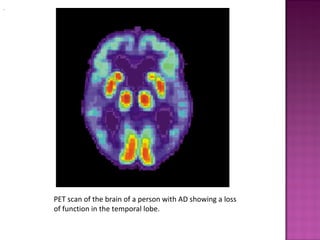

 Advanced medical imaging with computed

tomography (CT) or magnetic resonance imaging

(MRI), and with single photon emission computer

tomography (SPECT) or positron emission tomography

(PET) can be used to help exclude other cerebral

pathology or subtypes of dementia.

PET scan of the brain of a person with AD showing a loss

of function in the temporal lobe.